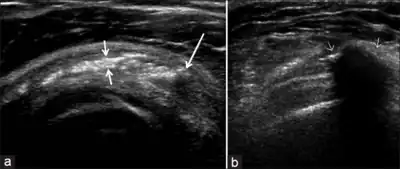

Calcific bursitis refers to calcium deposits within the bursae. This most occurs in the shoulder area. The most common bursa for calcific bursitis to occur is the subacromial bursa. A bursa is a small, fluid-filled sac that reduces friction, and facilitates movements between its adjacent tissues (i.e., between tendon and bone, two muscles or skin and bone). Inflammation of the bursae is called bursitis.

Diagnosis

Diagnostic methods are the following